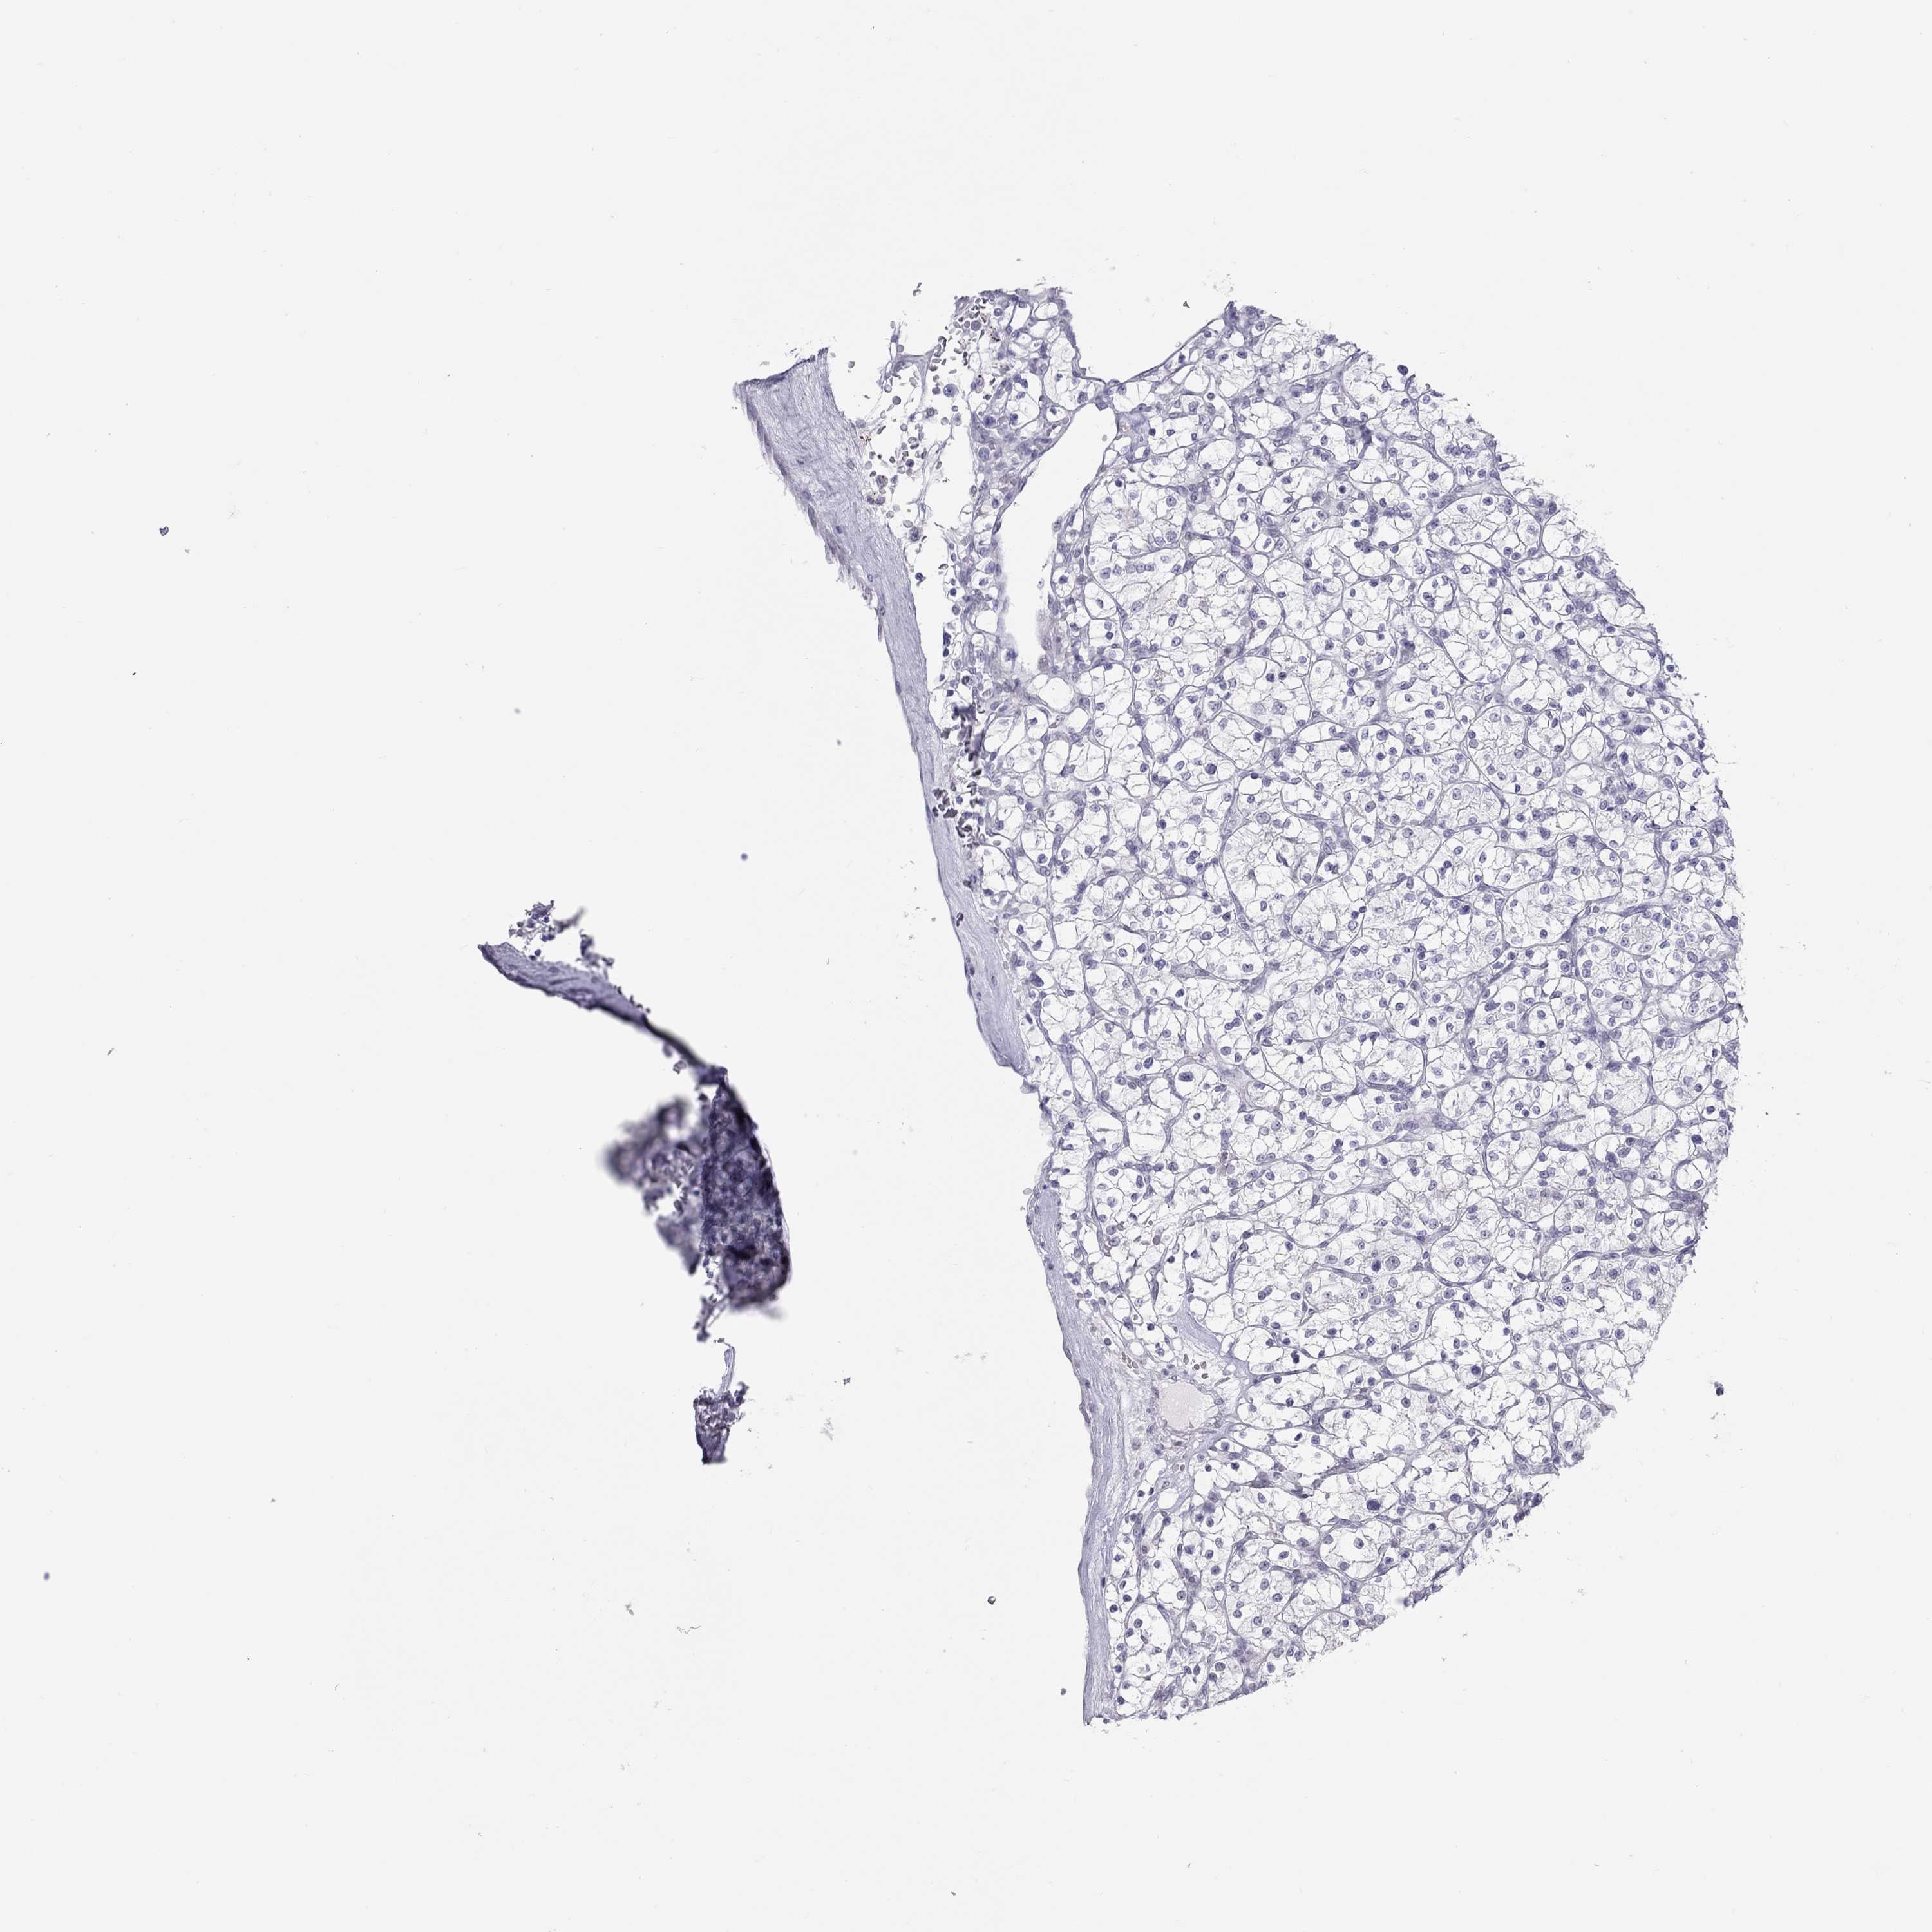

CANCER RENAL CANCER Show tissue menu

KICH TCGA KIRC TCGA KIRC VALIDATION KIRP TCGA PROTEIN RCC CPTAC PROTEIN EXPRESSION

Kidney chromophobe

KIDNEY CHROMOPHOBE (TCGA) - Interactive survival scatter ploti

The Survival Scatter plot shows the clinical status (i.e. dead or alive) for all individuals in the patient cohort, based on the same data that underlies the corresponding Kaplan-Meier plots. Patients that are alive at last time for follow-up are shown in blue and patients who have died during the study are shown in red.

The x-axis shows the expression levels (FPKM) of the investigated gene in the tumor tissue at the time of diagnosis. The y-axis shows the follow-up time after diagnosis (years). Both axes are complimented with kernel density curves demonstrating the data density over the axes. The top density plot shows the expression levels (FPKM) distribution among dead (red) and alive patients (blue). The right density plot shows the data density of the survived years of dead patients with high and low expression levels respectively, stratified using the cutoff indicated by the vertical dashed line through the Survival Scatter plot. This cutoff is automatically defined based on the FPKM cutoff that minimizes the p-score. The cutoff can be changed by dragging the vertical line or by entering a cutoff value in the square labeled "Current cut-off".

Under the Survival Scatter plot the p-score landscape (black curve; left axis) is shown together with dead median separation (red curve; right axis). Dead median separation is the difference in median mRNA expression between patients who have died with high and low expression, respectively. It is calculated as follows: median FPKM expression of dead patients with high expression - median FPKM expression of dead patients with low expression. This is intended to aid the user in visually exploring custom cutoffs and the associated p-scores and dead median separation.

Individual patient data is displayed and can be filtered by clicking on one or more of the category buttons on the top of the page. Categories describing expression level and patient information include: high, low, alive, dead, female, male and tumor stages. The scale of the x-axis can be toggled between linear and log-scale by clicking on the "x log" button. Mouse-over function shows TCGA ID, patient information and mRNA expression (FPKM) for each patient.

& Survival analysisi

Kaplan-Meier plots summarize results from analysis of correlation between mRNA expression level and patient survival. Patients were divided based on level of expression into one of the two groups "low" (under cut off) or "high" (over cut off). X-axis shows time for survival (years) and y-axis shows the probability of survival, where 1.0 corresponds to 100 percent.

JHY is not prognostic in Kidney Chromophobe (TCGA)

Best expression cut offi

Based on the FPKM value of each gene, patients were classified into two groups and association between prognosis (survival) and gene expression (FPKM) was examined. The best expression cut-off refers the FPKM value that yields maximal difference with regard to survival between the two groups at the lowest log-rank P-value. Best expression cut-off was selected based on survival analysis .

When clicking on this number, the vertical dashed line indicating cut-off, the interactive survival plot, and the Kaplan-Meier curve will be adjusted to show results based on the best expression cut-off.

: 2.27

Median expressioni

Median expression refers to the median FPKM value calculated based on the gene expression (FPKM) data from all patients in this dataset. When clicking on this number, the vertical dashed line indicating cut-off, the interactive survival plot, and the Kaplan-Meier curve will be adjusted to show results based on the median expression.

: N/A

Median follow up timei

Median follow up time refers to the median time (years) after diagnosis with this type of cancer, based on clinical data from all patients in this dataset.

P scorei

Log-rank P value for Kaplan-Meier plot showing results from analysis of correlation between mRNA expression level and patient survival.

N/A

5-year survival highi

5-year survival for patients with higher expression than the expression cutoff.

For melanoma and glioma, 3-year survival is shown.

5-year survival lowi

5-year survival for patients with lower expression than the expression cutoff.

TCGA RNA samplesi

RNA-seq data is reported as average FPKM (number Fragments Per Kilobase of exon per Million reads), generated by the The Cancer Genome Atlas (TCGA) .

Normal distribution across the dataset is visualized with box plots, shown as median and 25th and 75th percentiles. Points are displayed as outliers if they are above or below 1.5 times the interquartile range. FPKM values of the individual samples are presented next to the box plot.

Average pTPM 2.4

Number of samples 64